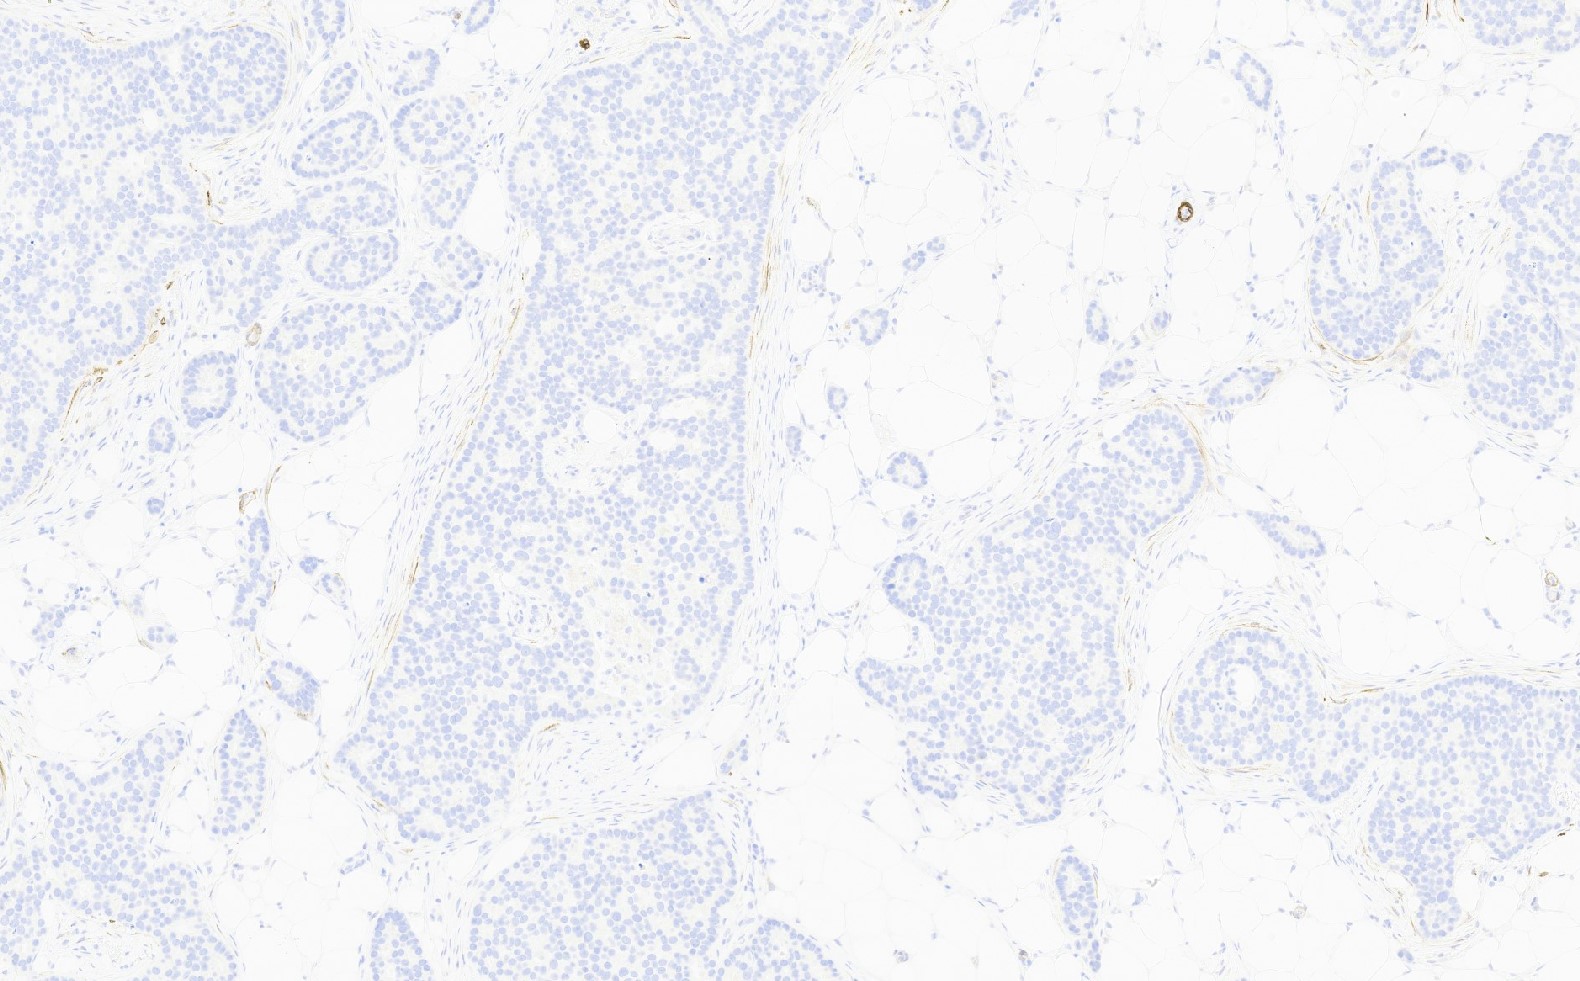

- No myoepithelial cell lining (as seen in DCIS or benign lesions)

- Angiolymphatic invasion in 35%; differs from tissue retraction because:

- Occurs outside margin of carcinoma

- Does not conform precisely to space it is in

- Endothelial lining is present and is CD31+, ERG, D2-40+, CD34+ and factor VIII+

Microscopic (histologic) images

Contributed by Julie M. Jorns, M.D., Kristen E. Muller, D.O., Gary Tozbikian, M.D. and Emad Rakha, M.D.

Negative stains

- CK20, CD34

- Myoepithelial markers: p63 (positive in benign lesions), CD10, calponin (Am J Surg Pathol 2001;25:1054, Mod Pathol 2002;15:397)

- Ductal carcinoma in situ involving sclerosing lesions (e.g., sclerosing adenosis):

- IHC using myoepithelial markers shows retained myoepithelial cell layer

A. Calponin and p63. The use of myoepithelial markers is most useful for distinguishing in situ from invasive carcinoma. Utilization of 2 myoepithelial markers, including both a cytoplasmic marker (e.g., calponin or smooth muscle myosin) and a nuclear marker (p63 or p40) is recommended, as myoepithelial expression can be patchy or attenuated (p63 / p40) and show nonspecific expression in endothelial cells (SMMS); the combination of 2 markers provides increased sensitivity and specificity. Both DCIS and invasive breast carcinoma (NST) may show expression of hormone receptors, HER2 and cytokeratins.